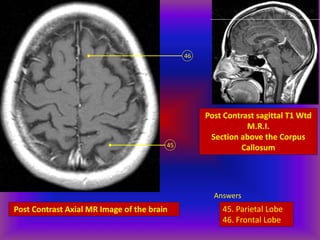

Post Contrast Axial MR Image of the brain

45

46

Post Contrast sagittal T1 Wtd

M.R.I.

Section above the Corpus

Callosum

Answers

45. Parietal Lobe

46. Frontal Lobe